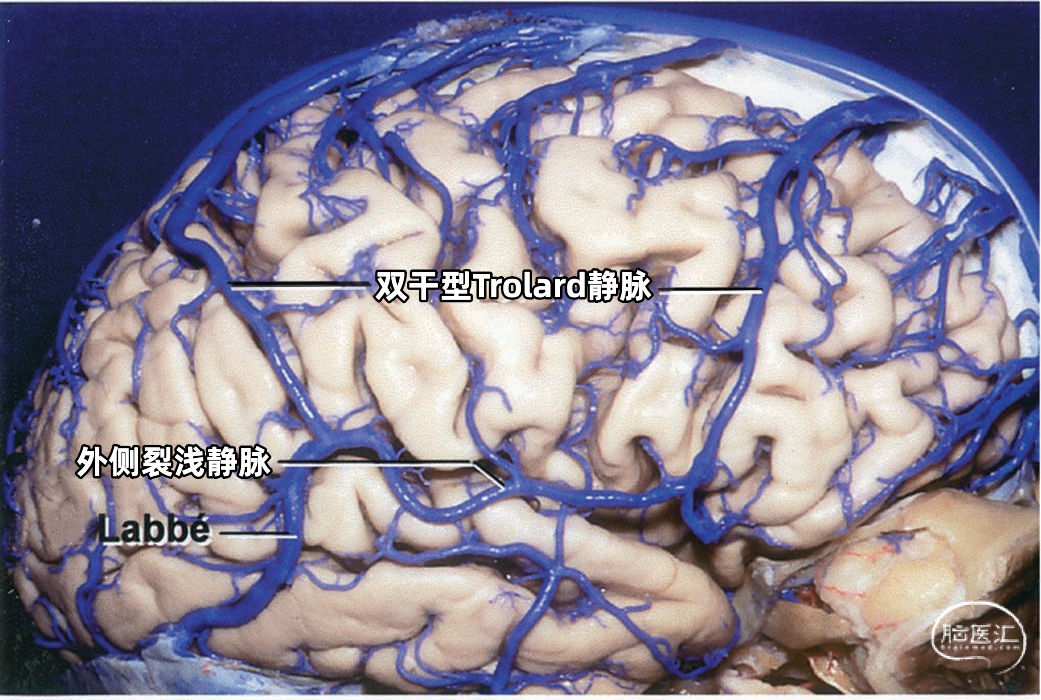

大脑外侧面最大的静脉是Trolard、Labbé、外侧裂浅静脉。 Trolard静脉是最粗大的吻合静脉,连接外侧裂静脉和上矢状窦。Labbé静脉则是连接外侧裂浅静脉和横窦的最粗大吻合静脉。外侧裂浅静脉沿外侧裂表面走行,而且主要沿蝶骨嵴汇入硬膜窦(蝶顶窦或海绵窦)。 虽然Trolard、Labbé静脉和外侧裂浅静脉大小可能相同,但更常见的是其中一支或两支血管比较粗大,而剩下的则细小甚至缺如。通常左右两侧血管的大小并不对称。

下图示三组吻合静脉,Trolard静脉和Labbé静脉为主要引流静脉。

Trolard静脉又称上吻合静脉,是跨越额叶和顶叶,连接外侧裂与上矢状窦的最大吻合静脉。 在我们研究的20例半球标本中,发现15例Trolard静脉的位置相当于中央前静脉、中央沟静脉和中央后静脉,最常见的位置是中央后静脉水平。最靠前的Trolard静脉位于额前静脉水平,连接上矢状窦的前部和外侧裂浅静脉的前部。最靠后的Trolard静脉位于顶前静脉水平。 Trolard静脉通常以单干向前走行,汇入上矢状窦,与血流相反方向。通常Troland静脉在将要汇入上矢状窦前接受其他一些静脉的回流,它的下端通常以单一通道与外侧裂静脉相沟通,但也可在额叶和顶叶凸面的下部分成许多分支加入外侧裂浅静脉。有时会有两条同样大小的Trolard静脉连接外侧裂血管和上矢状窦之间。

下图示(左侧半球)外侧裂浅静脉与Labbé静脉之间有较大的吻合支。另外,有两支或双干型的Trolard静脉属支连接上矢状窦和外侧裂静脉,后方一支Trolard静脉在外侧裂浅静脉与Labbé静脉的结合处附近加入外侧裂浅静脉。

下图示(右侧半球)双干型的Trolard静脉连接于上矢状窦和外侧裂之间,一支越过额叶,另一支越过顶叶。外侧裂浅静脉与Labbé静脉之间也有一个粗大的吻合支。

下图示(右侧半球)没有明显的外侧裂浅静脉。有双干型Labbé静脉从外侧裂到横窦。中央沟静脉和额后静脉的大小几乎相同,组成双干型Trolard静脉,连接外侧裂和上矢状窦。中央沟静脉下部走行于中央沟内。

下图示双干型Trolard静脉和双干型Labbé静脉引流外侧裂附近的大部分静脉。